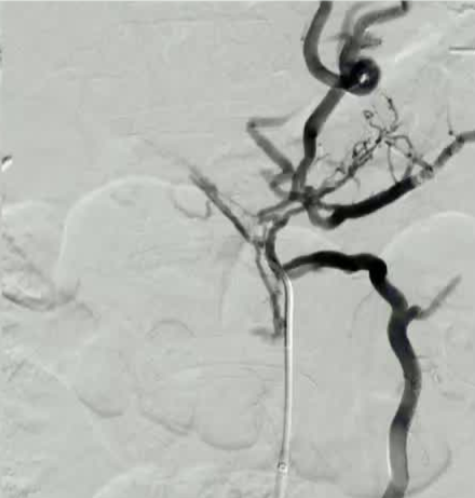

成功实现了经肝通路对门静脉系统的接入,但该接入方式显示出的是一个迂曲的肝周静脉网,且没有合适的肝内门静脉靶点用于进行经颈静脉肝内门体分流术(TIPS)的置入。因此,决定寻找其他途径接入门静脉系统,以便在 TIPS 术前进行再通处理。 通过有限的脐上剖腹探查术,在直视下对肠系膜上静脉的一个分支进行了插管,从而能够置入一个 6 号规格的鞘管。 随后通过该通道实现了对中央/肝内门静脉的直接再通。接着,从肝门静脉窦通道取出一个套管,将其置入肝内门静脉系统,从而能够从中肝静脉进行穿刺操作。 凭借这一通道,椎间盘源性疼痛的手术置入操作得以顺利完成。 患者开始使用克赛(lovenox),并在手术后 3 天出院。 该患者无需再次进行腹腔穿刺,但在经颈静脉肝内门体分流术(TIPS)术后 2.5 个月,因中再次央门静脉狭窄接受了 TIPS 血管成形术并置入了中央支架延伸段。 此病例展示了在慢性中央门静脉血栓形成等复杂情况下通往门静脉系统的其他通路,从而能够进行经颈静脉肝内门体分流术(TIPS)的实施,并对门静脉高压症进行治疗。 1) 传统的门静脉通路方法包括经颈静脉、经皮经肝以及经皮穿刺脾内通路等。 2)若经颈静脉、经肝和经脾的通路均无法使用,则可考虑采用经肠系膜静脉通路进行操作。 3)在腹腔镜手术辅助下或开腹SMV穿刺术,是一种适用于慢性门静脉再通手术的、安全的门静脉穿刺方法。 除了开腹肠系膜静脉或腹腔镜下肠系膜静脉穿刺,也有作者探讨经皮超声引导下穿刺的安全性